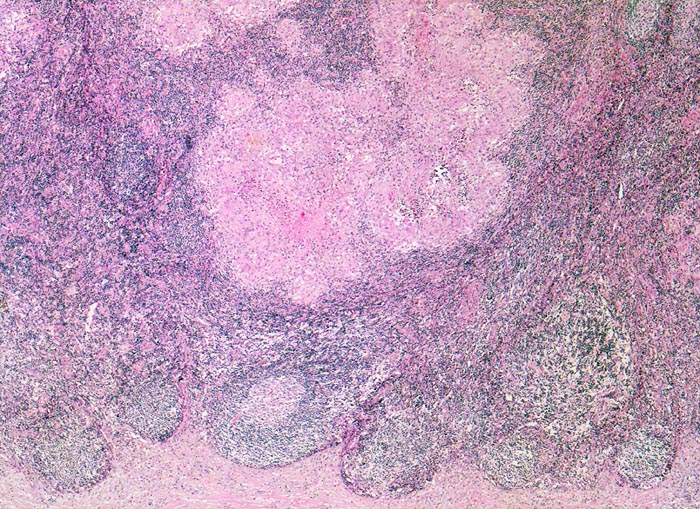

PathoPic – image database / PathoPic ID 4254 - retikulozytär-abszedierende Lymphadenitis bei Katzenkratzkrankheit

retikulozytär-abszedierende Lymphadenitis bei Katzenkratzkrankheit

Entzündung infektiös

Lymphknoten, Axilla

Beschreibung

Nachweis von kleinen pleomorphen Bakterien

Druckschmerzhafte Lymphknotenvergrösserung in der rechten Axilla 2 Wochen nachdem der Patient von seiner Katze an der rechten Hand gekratzt wurde.

Keine käsige Nekrose wie bei Tbc.

Histologie

25